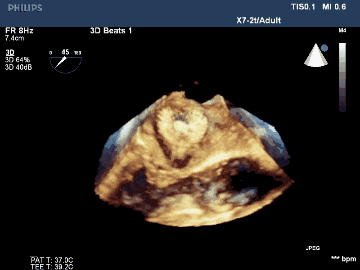

葛均波院士、周達新教授等經(jīng)詳細評估和討論后,認為該受試者需要植入固定部20mm、封堵盤28mm的左心耳封堵器,為非常規(guī)固配規(guī)格,SimuLock的可選配組裝式設(shè)計精準滿足患者需求。

手術(shù)過程順利,通過植入非常規(guī)固配規(guī)格的固定部20mm、封堵盤28mm的左心耳封堵器,實現(xiàn)左心耳完全封堵,達到手術(shù)預(yù)期效果,再次體現(xiàn)產(chǎn)品獨特的設(shè)計創(chuàng)新優(yōu)勢。

術(shù)后TEE三維重建影像示封堵器位置佳,封堵完全